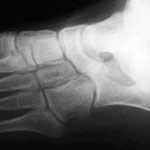

1. Radiologie conventionnelle

L’apport de la radiologie conventionnelle est de mettre directement en évidence la synostose (signes directs) ou de révéler une série de variations morphologiques dont certaines sont en relation plus ou moins directe avec des troubles de la mobilité du pied, y compris les lésions de coalition du tarse.

Tout patient suspect de synostose du tarse sera d’abord exploré par 3 incidences : face, profil et incidence ¾ externe ou spéciale « oblique » à 45°.

L’incidence oblique est la meilleure pour rechercher les barres CN (Fig.1 et 9). Elle est réalisée à 45°, mais peut être complétée par d’autres clichés d’obliquité quelque peu différente afin de supprimer des superpositions trompeuses (46,15).

La présence d’une barre peut être attestée par :

• l’existence d’un pont osseux plus ou moins complet et régulier (Fig.9-a et b);

• un aspect de « pseudarthrose » avec des berges condensées, irrégulières et/ou une sclérose corticale entre le processus antéro-médial du calcanéum et la partie latérale de l’os naviculaire (46) (Fig.9-c);

• la présence d’un processus volumineux ou trop long s’insinuant à moins de 5 mm du naviculaire associé à des signes secondaires et à une clinique évocatrice feront suspecter un « bec calcanéen long » (25) (Fig.9-d).

Ce bilan est fréquemment suffisant en particulier dans les formes CN (56 diagnostics sur 68 cas dans le travail de ROUVREAU (52) et 100 % des cas dans celui de GONZALEZ (23)).